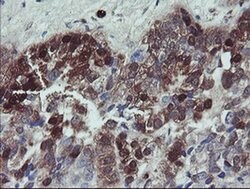

TSC22D1 Monoclonal Antibody (OTI1A5), Invitrogen™

Supplier: Thermo Scientific MA526037

| Immunohistochemistry (Paraffin), Western Blot | |